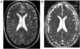

Hemiparesis, or unilateral paresis, is weakness of one entire side of the body (hemi- means "half"). Hemiplegia is, in its most severe form, complete paralysis of half of the body. [Source: Wikipedia ]